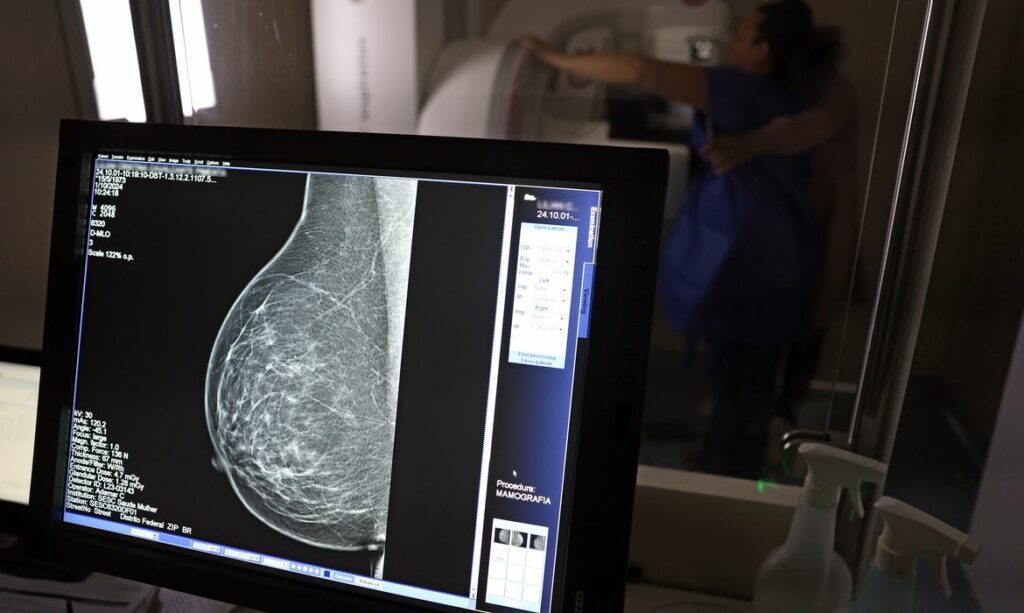

O acesso a exames de mamografia no Brasil revela uma acentuada desigualdade, com a rede pública oferecendo consideravelmente menos equipamentos do que o setor privado. Essa disparidade, evidenciada por um relatório recente, representa um obstáculo significativo à detecção precoce do câncer de mama, uma doença que demanda rastreamento e tratamento equitativos para reduzir a mortalidade.

Um levantamento detalhado do Atlas da Radiologia no Brasil, elaborado pelo Colégio Brasileiro de Radiologia e Diagnóstico por Imagem (CBR), destaca que, embora o país disponha de 6.826 equipamentos de mamografia registrados – com 96% em pleno funcionamento –, a distribuição é extremamente desbalanceada. O Sistema Único de Saúde (SUS), que atende cerca de 75% da população brasileira, possui apenas metade desses aparelhos. Consequentemente, a proporção é de 2,13 mamógrafos para cada 100 mil habitantes dependentes do SUS.

Em contraste, o cenário na saúde suplementar, que abrange os restantes 25% da população, é substancialmente mais favorável. Neste setor, observam-se 6,54 aparelhos para cada 100 mil beneficiárias, o que representa quase o triplo da oferta encontrada na rede pública. O estado do Acre serve como um exemplo gritante dessa disparidade, registrando 35,38 mamógrafos por 100 mil habitantes na rede privada, enquanto o SUS oferece uma taxa de apenas 0,84.

Com a estimativa do Instituto Nacional do Câncer (INCA) de mais de 73 mil novos diagnósticos de câncer de mama anualmente no Brasil, a detecção precoce assume um papel vital. Em setembro, o Ministério da Saúde ampliou as diretrizes de rastreamento, agora recomendando que mulheres entre 40 e 49 anos, mesmo sem sintomas, realizem mamografias regulares.

Conforme Ivie Braga de Paula, a eficácia na redução da mortalidade está diretamente ligada à descoberta do tumor antes do aparecimento de sintomas clínicos. Quanto menor o tamanho do tumor, melhores são as opções de tratamento e maiores as chances de cura. Portanto, a mamografia é a ferramenta primordial para identificar esses tumores em estágios iniciais.

Em conclusão, a especialista ressalta que um câncer de mama diagnosticado com menos de 1 centímetro oferece uma chance de cura de 95% em cinco anos, independentemente de sua agressividade. Esses tumores, detectáveis apenas pela mamografia, sublinham a importância de que mulheres saudáveis, e não apenas aquelas com sintomas, procurem ativamente esse exame preventivo.